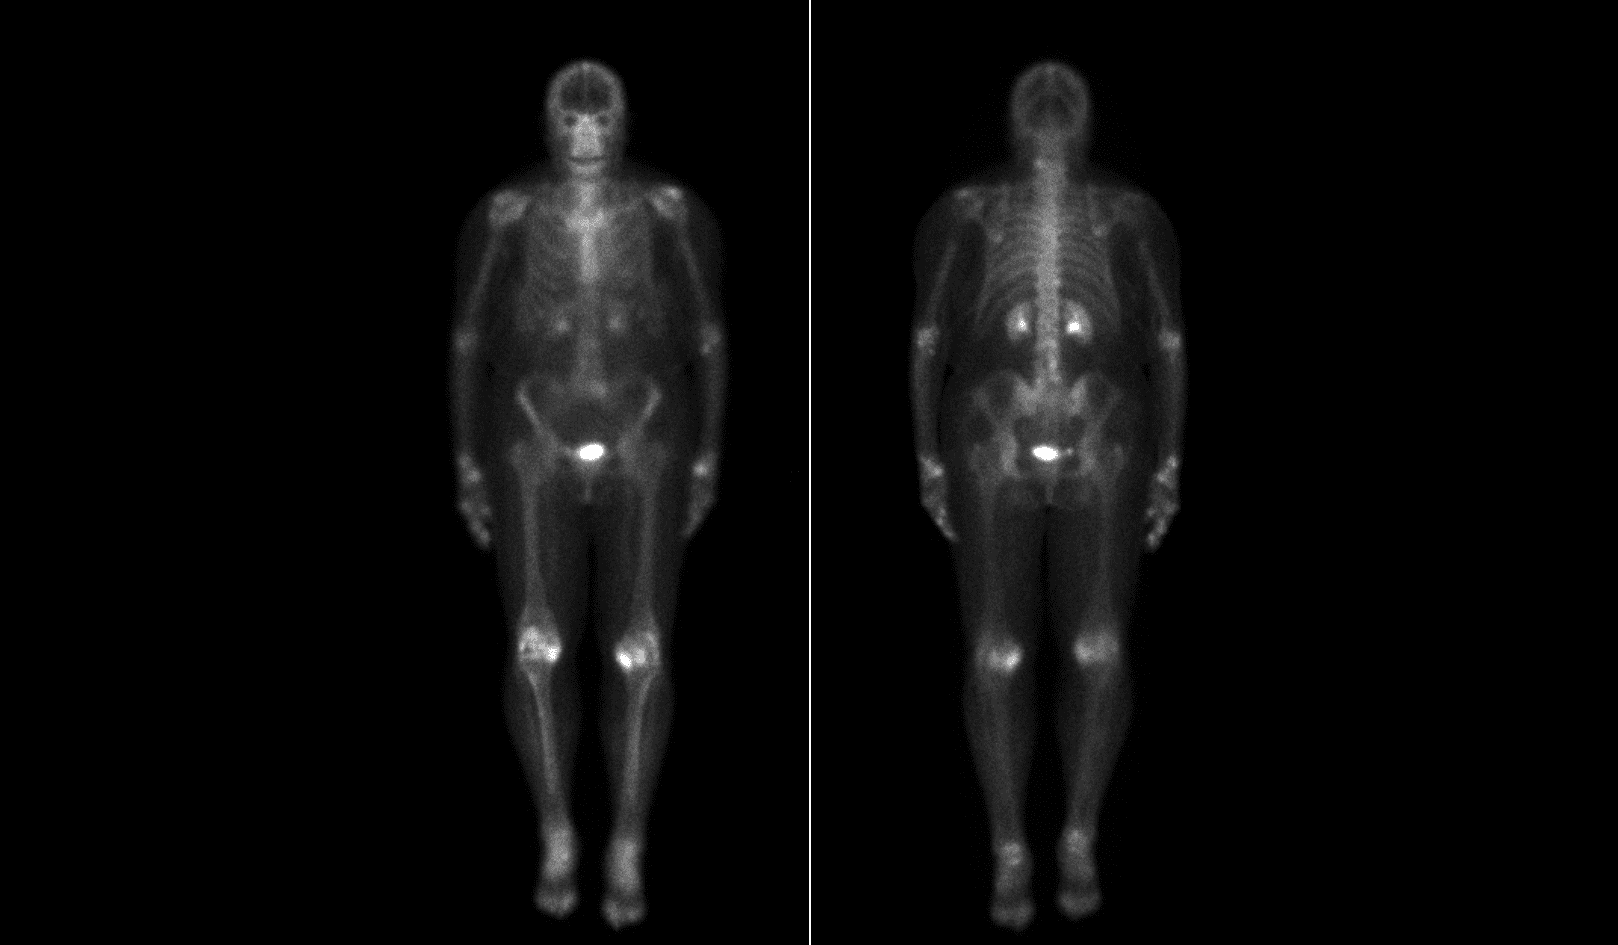

Moses Campus, along with Children’s Hospital at Montefiore Einstein, features 726 adult inpatient beds and 106 pediatric inpatient beds. The facility also offers services to outpatients. As an NCI-Designated Cancer Center, Moses provides diagnostic and therapeutic modalities through an active theranostics program. While training at Moses, residents partake in a particularly rigorous program in oncologic and non-oncologic pediatric and adult nuclear medicine. Our Transplant Center, also on-site, affords residents the ability to evaluate organ physiology pre- and post-transplant.